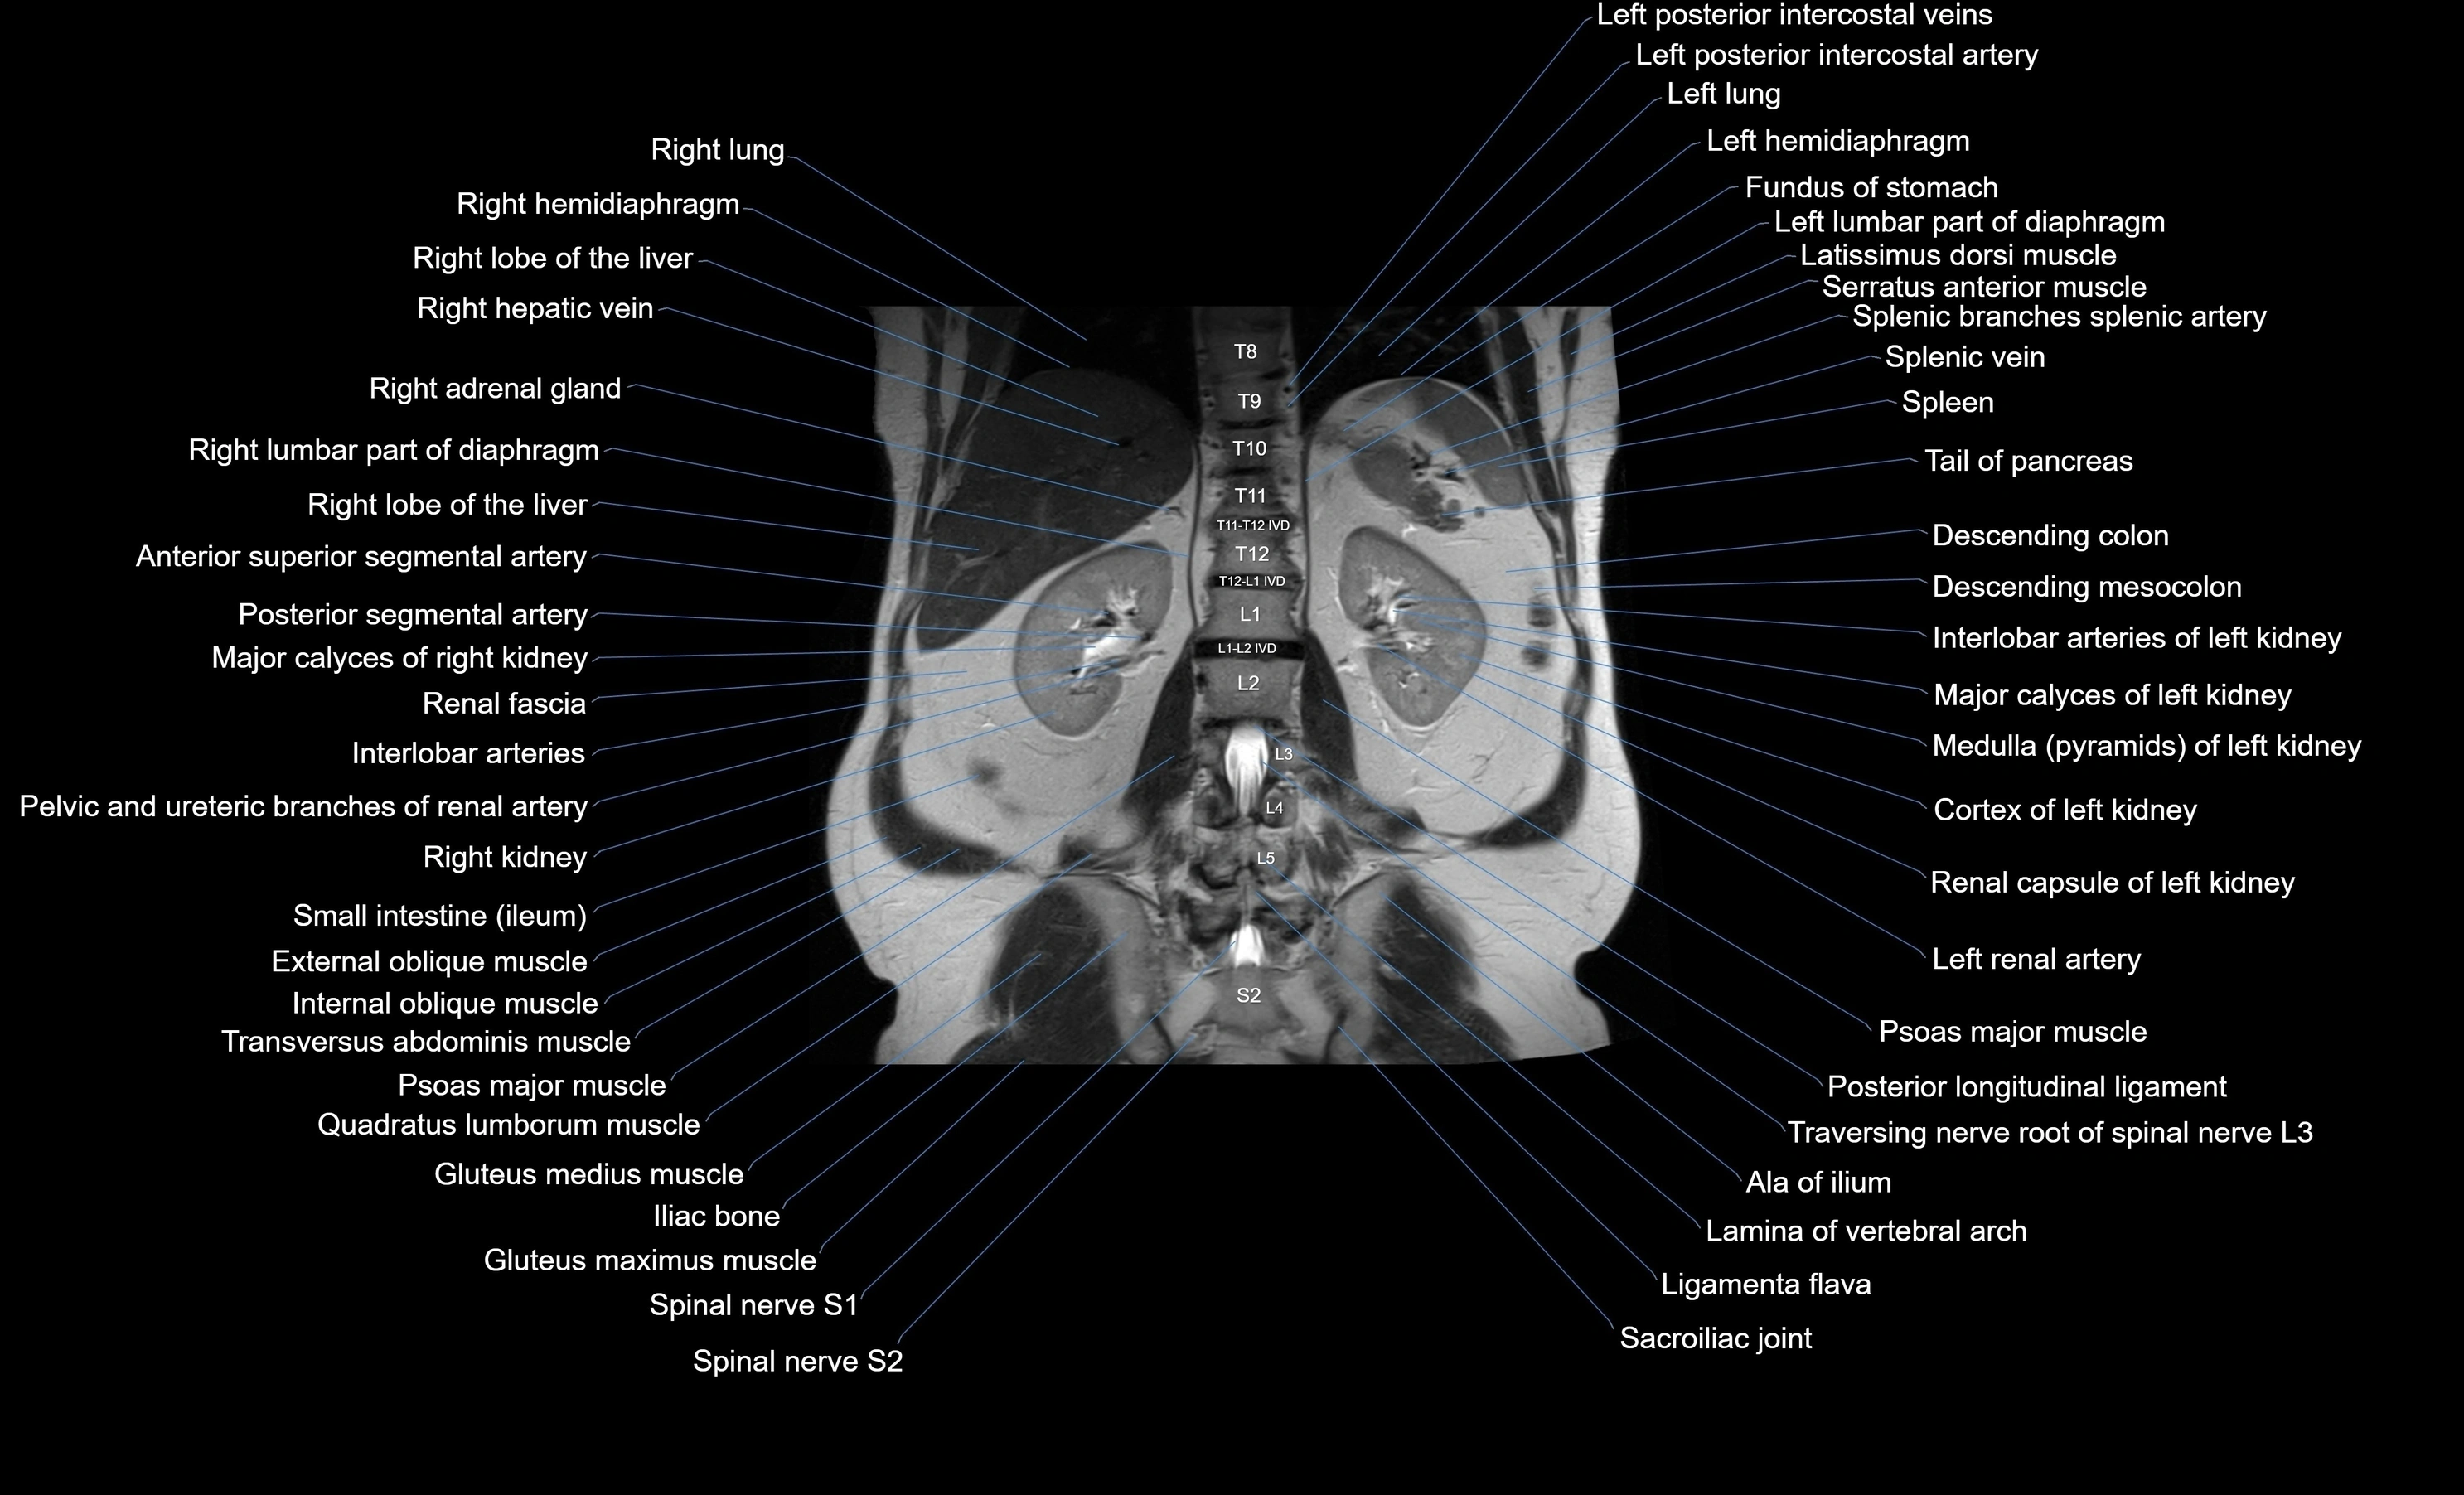

MRI images